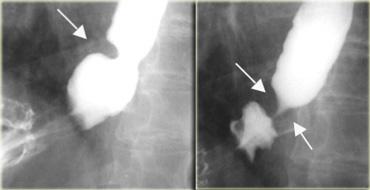

Túi thừa Zenker

Túi thừa Zenker là túi thừa giả hạ họng do áp lực, trong đó chỉ có lớp niêm mạc và dưới niêm mạc nhô qua điểm yếu hình tam giác ở thành sau (khe hở Killian) nằm giữa các thành phần ngang và chéo của cơ nhẫn-hầu.

Nguyên nhân còn gây tranh cãi, có thể do tăng áp lực thực quản trên, rối loạn chức năng cơ nhẫn-hầu và trào ngược.

Biểu hiện lâm sàng có thể là khó nuốt, trào ngược, hít sặc hoặc xuất hiện khối hay mức khí-dịch trên phim X-quang cổ hoặc ngực.

Chụp thực quản cản quang cho thấy hình ảnh túi chứa có nguồn gốc từ đường giữa phía sau, ngay trên cơ nhẫn-hầu, nhô sang bên (thường sang trái) và xuống dưới, kích thước tăng dần.

Túi thừa Killian-Jamieson là túi thừa do áp lực, nhô qua điểm yếu giải phẫu ở mặt bên của thực quản cổ, phía dưới cơ nhẫn-hầu, khác với túi thừa Zenker có nguồn gốc từ đường giữa phía sau.

Hình chiếu thẳng (AP) cho thấy túi thừa (mũi tên) xuất phát từ phía bên.

Hình chiếu nghiêng xác nhận túi thừa không xuất phát từ phía sau như túi thừa Zenker.

TRÁI: Túi thừa nhỏ (mũi tên) ở bệnh nhân không có triệu chứng. PHẢI: Túi thừa lớn (mũi tên) ở bệnh nhân có hít sặc